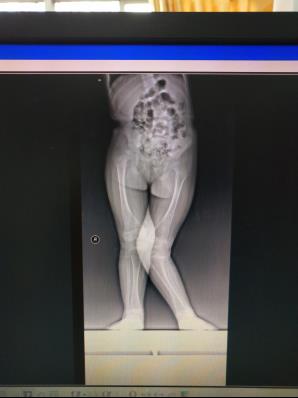

儿童下肢畸形

儿童下肢膝外翻畸形应用“8”字钢板骨骺阻滞术,效果满意

儿童股骨头缺血性坏死

儿童股骨头缺血性坏死行粗隆下内翻截骨钢板内固定治疗,增加股骨头包容,效果满意。图是CT片